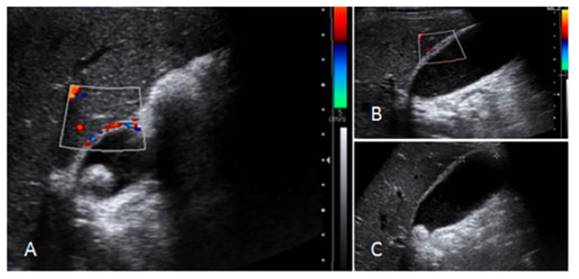

El diagnóstico está compuesto por una combinación de parámetros clínicos, bioquímicos y radiológicos. El ultrasonido abdominal ha demostrado ser el método con mejor costo-efectividad (figuras 2), y a pesar de que la gammagrafía con ácido iminodiacético hepatobiliar (HIDA, por sus siglas en inglés), es considerada el estándar de oro, su disponibilidad es limitada.(4)

Fuente: Morales 2021

Figura 2. Imágenes de diagnóstico